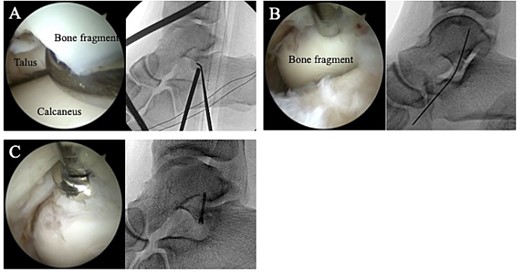

The surgery was performed under general anesthesia in the lateral position, with the affected side up. A thigh air tourniquet and a fluoroscopy were used. First, 3 ml of normal saline was injected into the sinus tarsi. A viewing portal was then made above the sinus tarsi, and a working portal was made 2 cm anterior to the viewing portal. A 30° arthroscope with a diameter of 2.7 mm was used to observe the fracture site (Fig. 3A). The synovium, adipose tissue and coagulation clot surrounding the fracture site were removed with a 3.0-mm-diameter motorized shaver, and the bone fragment was reduced using a guidewire sleeve and fixed with a 0.8-mm guidewire (Fig. 3B), the fragment was fixed through the guidewire with a cannulated double-threaded screw (Double Thread Screw Japan Mini, Meira, Nagoya, Japan) (Fig. 3C). After confirming that the bone fragment was fixed in the correct position under a fluoroscopy, the wound was sutured, and so the surgery was concluded (Fig. 4).

(A) A 30° arthroscope with a diameter of 2.7 mm was used to observe the fracture site. (B) The bone fragment was reduced using a guidewire sleeve and fixed with a 0.8-mm guidewire. (C) The fragment was fixed through the guidewire with a cannulated double-threaded screw.